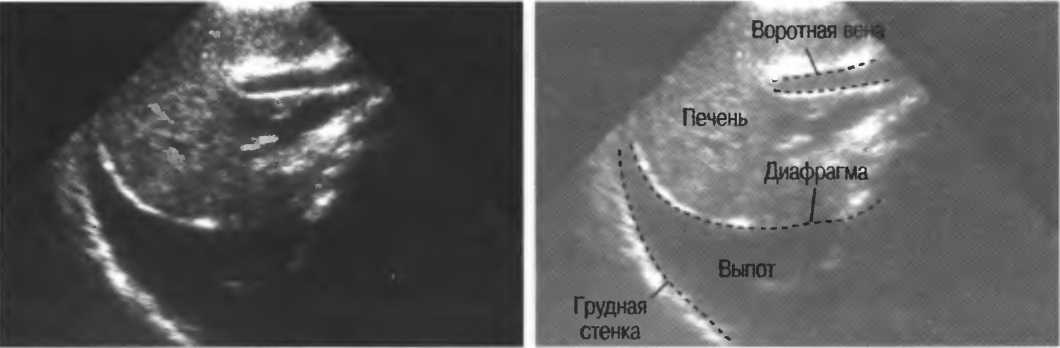

в Найроби, коллективу Найробийского рентгенологического центра;